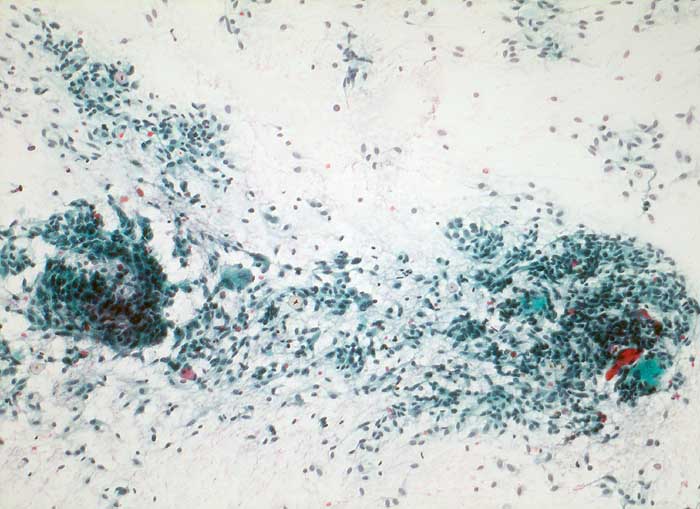

medulläres Schilddrüsenkarzinom

Frischgewebsabstrich: Sehr zellreicher Ausstrich mit grösseren Verbänden spindeliger Zellen und wenig Kolloid.

Patient aus MEN IIA-Familie mit nachgewiesener Mutation des RET-Protoonkogens. Erhöhte Calcitoninwerte nach Pentagastrinstimulation und dringender V.a. medulläres Schilddrüsenkarzinom rechts.

Zytologische Diagnose: medulläres Schilddrüsenkarzinom